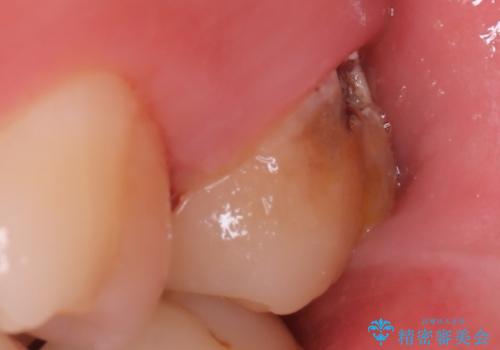

保険適用のメタルインレーと歯質の境目にう窩ができており、補綴物のやり替えとなりなした。

メタルインレーを除去したところう窩が深く、遠心の健歯質が歯肉縁下深くに位置したためディスタルウェッジ術を行い骨と歯肉の高さを下げた上で補綴しています。

元々インレーが入っていましたが、残存歯質量が少なく破折のリスクを説明しジルコニアクラウンでのやり替えとなりました。